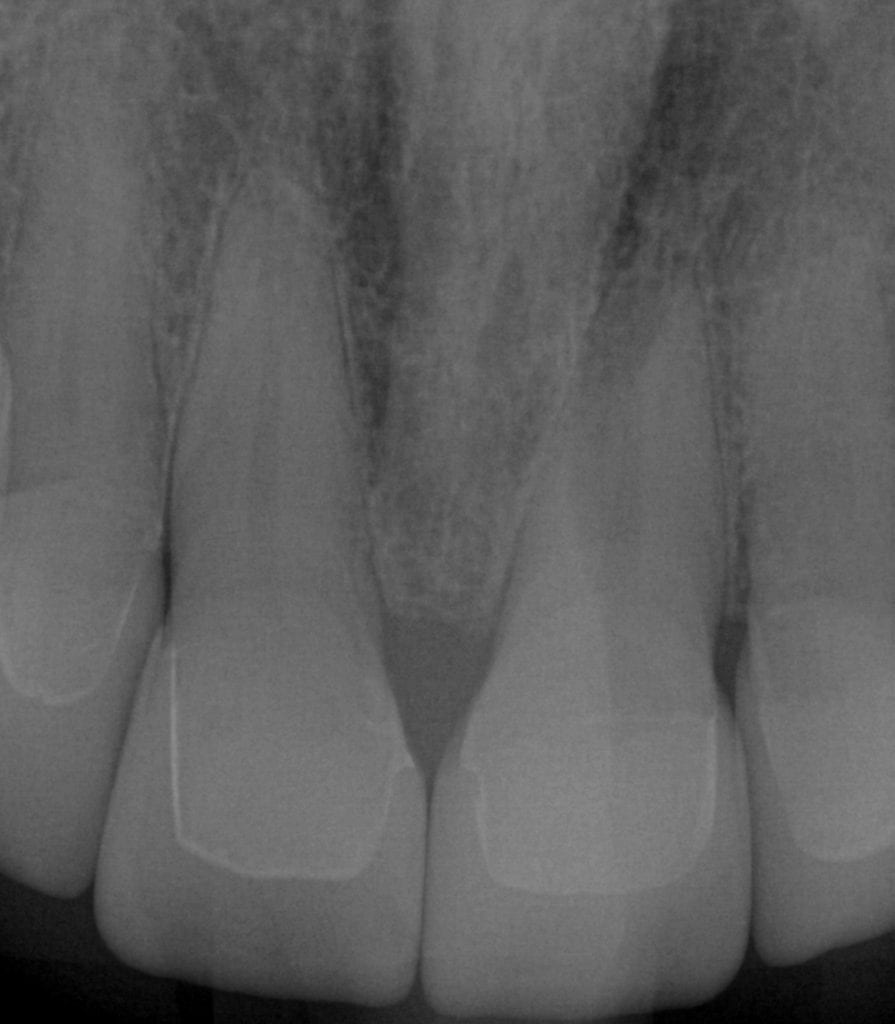

ONE WEEK POST-OP RADIOGRAPHS / CEMENT CHECK